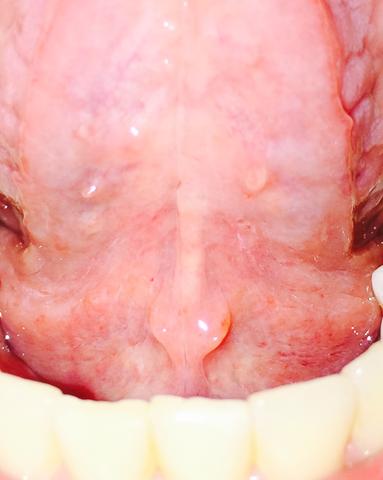

Was Habe Ich Unter Der Zunge Gesundheit Und Medizin